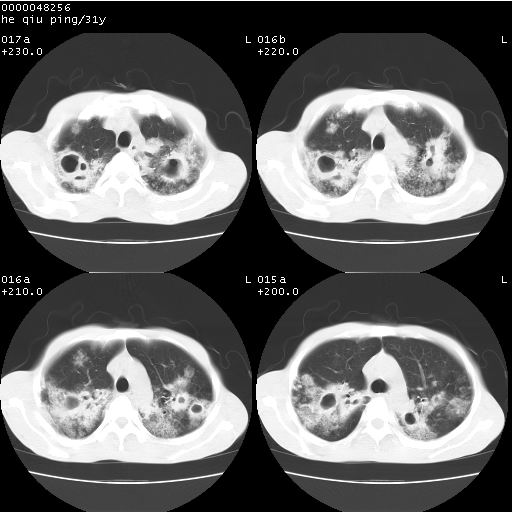

标题: CT13402:M,31Y。肺结核伴空洞形成? [打印本页]

标题: CT13402:M,31Y。肺结核伴空洞形成?

咳嗽半月余,消瘦体质,呼吸音弱。无其他病史。cr:肺转移瘤待。

双上肺多发空洞,双飞散在分布大小不一的片状结高密度影节状大片状高密度影。符合结合肉芽肿形成及空洞形成。

双侧弥漫性病变,双上叶尖后段、下叶北段见多个空洞,多见于结核感染。右中叶及双下叶斑片状,结节状影,考虑为肉芽肿形成及支气管播散。但由于患者消瘦体质,抵抗力低下,若继发感染,如金葡菌肺炎也有可能。

考虑为:两肺结核伴多发空洞形成、支气管播散。

结核空洞并播散,玫瑰花簇征。

病灶多形性,有空洞形成。考虑肺结核伴空洞形成,两下肺支气管播散!